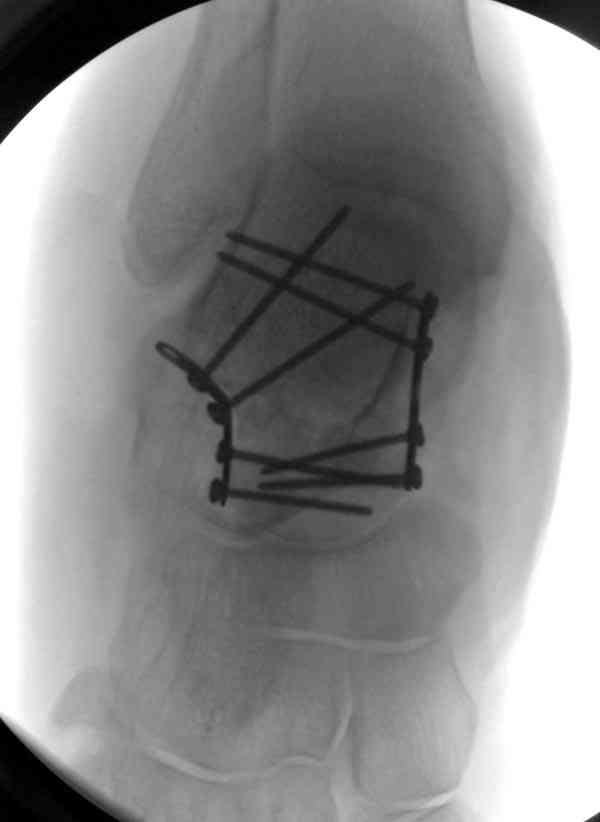

Случай с множественным оскольчатым переломом тарана оперированный из двойного доступа.

Через 8 мес.: